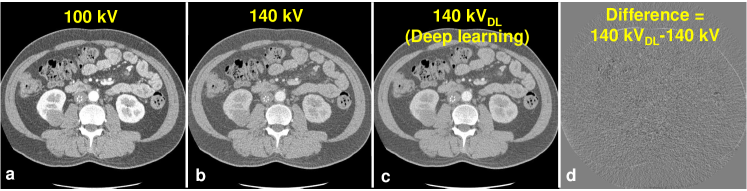

We found that the mapping CNN yields inferior high-energy CT images with original noisy low-energy CT images as input, indicating the CNN wastes its ability of expression on mapping the image difference between high- and low-energy levels with the presence of noise. With noise significantly reduced DECT images, the CNN can appreciate the ingenuous CT image difference at different energy levels and ultimately yield superior high-energy CT image. An example image slice is shown in Fig. 2. The HU difference between the predicted and original high-energy CT images are 3.47 HU, 2.95 HU, 2.38 HU and 2.40 HU for ROIs on spine, aorta, liver and stomach, respectively. Fig. 3 shows the three-dimensional VNC images and iodine maps obtained from original 100 kV/140 kV DECT images and deep learning-based DECT images. As can be seen, the deep learning-based DECT approach provides high quality VNC and iodine maps. Since material decomposition uses matrix inversion and yields amplified image noise, the noise levels in VNC images and iodine maps obtained from the original DECT images are much higher than the 100 kV images. Due to the noise correlation between the predicted high-energy CT images and the original low-energy CT images, deep learning-based DECT imaging provides noise significantly reduced VNC images and iodine maps. The HU differences between VNC images obtained from original DECT and deep learning DECT are 4.10 HU, 3.75 HU, 2.33 HU and 2.92 HU for ROIs on spine, aorta, liver and stomach, respectively. The aorta iodine quantification difference between iodine maps obtained from original DECT and deep learning DECT images is 0.9%, suggesting high consistency between the predicted and the original high-energy CT images.